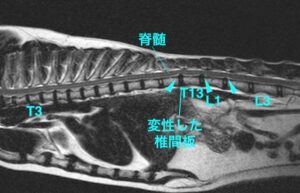

神経の検査では後ろ足の麻痺を認め、左よりも右後ろ足の麻痺がより強かった。レントゲン検査では明らかな異常はなく、脊髄(神経)の疾患が疑われ、MRI検査を実施。

椎間板の変形(左画像で黒い部分)が複数認められた。

また胸と腰の間の部分で脊髄を圧迫している初見が認められ、椎間板ヘルニアが疑われた。